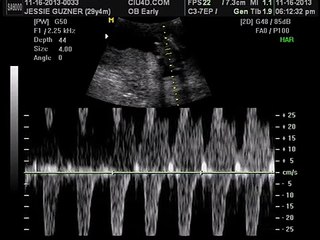

18 weeks pregnant, 18 weeks pregnant symptoms, 18 weeks pregnant ultrasound

User: Pregnant Woman